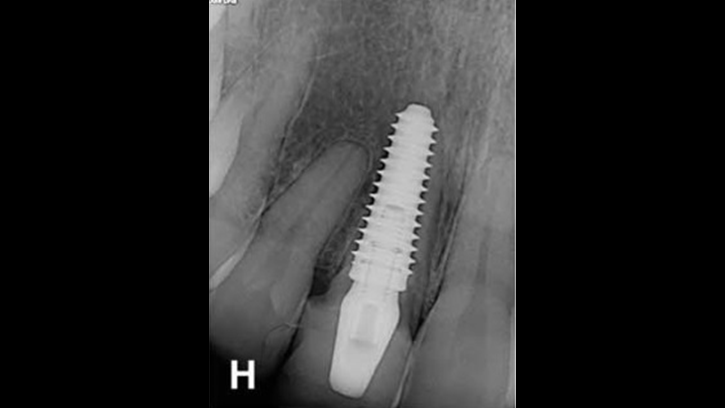

Clinical case: Replacement of fractured central incisor (#11) with immediate implant

& Root Membrane Technique

- Courtesy of Dr. Miltiadis Mitsias, Greece -

AnyRidge, Root Membrane Technique, retrospective study, long-term study, immediate implants, bone resorption, bone preservation, Dr. Miltiadis Mitsias,survival, success, maxillary anterior, single replacement

AnyRidge implant system, Root Membrane kit

The Root Membrane Technique: A retrospective clinical study with up to 10 years of follow-up./Implant Dent. 2018 Oct;27(5):564-574

https://www.ncbi.nlm.nih.gov/pubmed/30161062